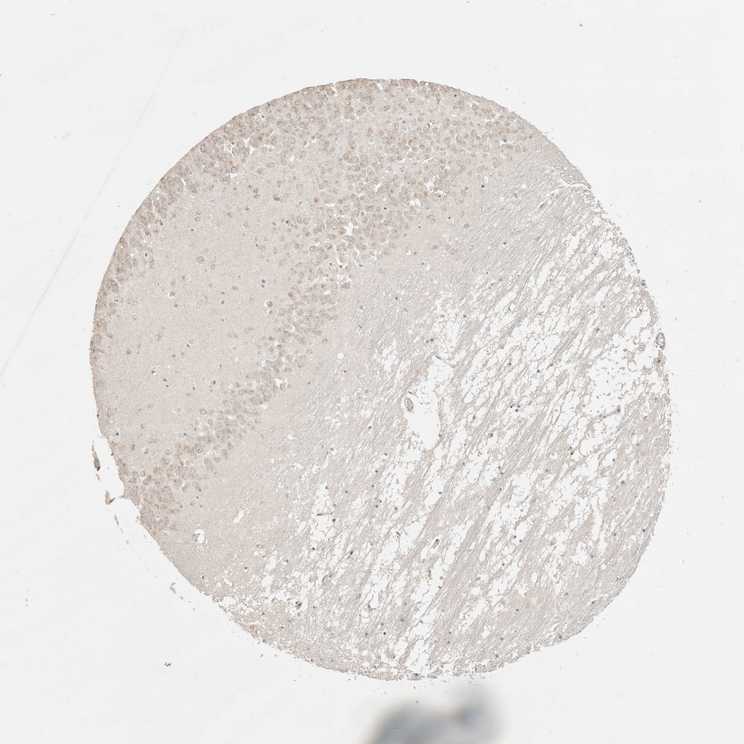

HIPPOCAMPUS - Antibody stainingi

Antibody staining in the annotated cell types in the current human tissue is reported as not detected, low, medium, or high, based on conventional immunohistochemistry profiling in selected tissues. This score is based on the combination of the staining intensity and fraction of stained cells.

Each image is clickable and will lead to virtual microscopy that enables deeper exploration of all samples and also displays staining intensity scores, fraction scores and subcellular localization as well as patient and tissue information for each sample.

Antibody HPA026995

Glial cells Not detected

Neuronal cells Medium